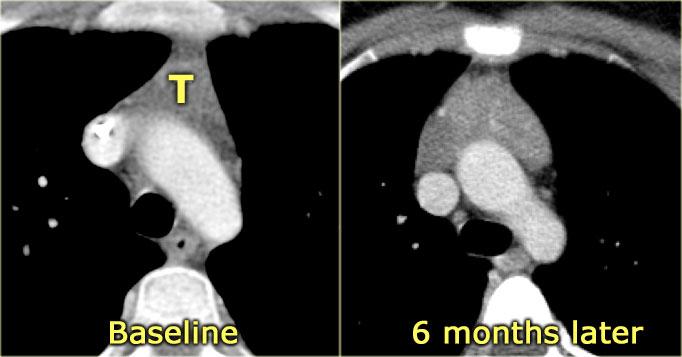

Trên CT, tăng sản biểu hiện là sự phì đại lan tỏa của tuyến ức, với sự bảo tồn hình dạng tam giác bình thường.

Định nghĩa tăng sản tuyến ức là thể tích tuyến ức tăng > 50%.

CT, MRI hoặc PET không thể phân biệt tăng sản phục hồi với thâm nhiễm tuyến ức do khối u.

Sự vắng mặt của các bệnh hoạt động khác và sự giảm dần kích thước tuyến ức trên các lần chụp CT nối tiếp hỗ trợ chẩn đoán tăng sản phục hồi.

Tuyến ức thường trở về kích thước bình thường trong 3 đến 6 tháng.